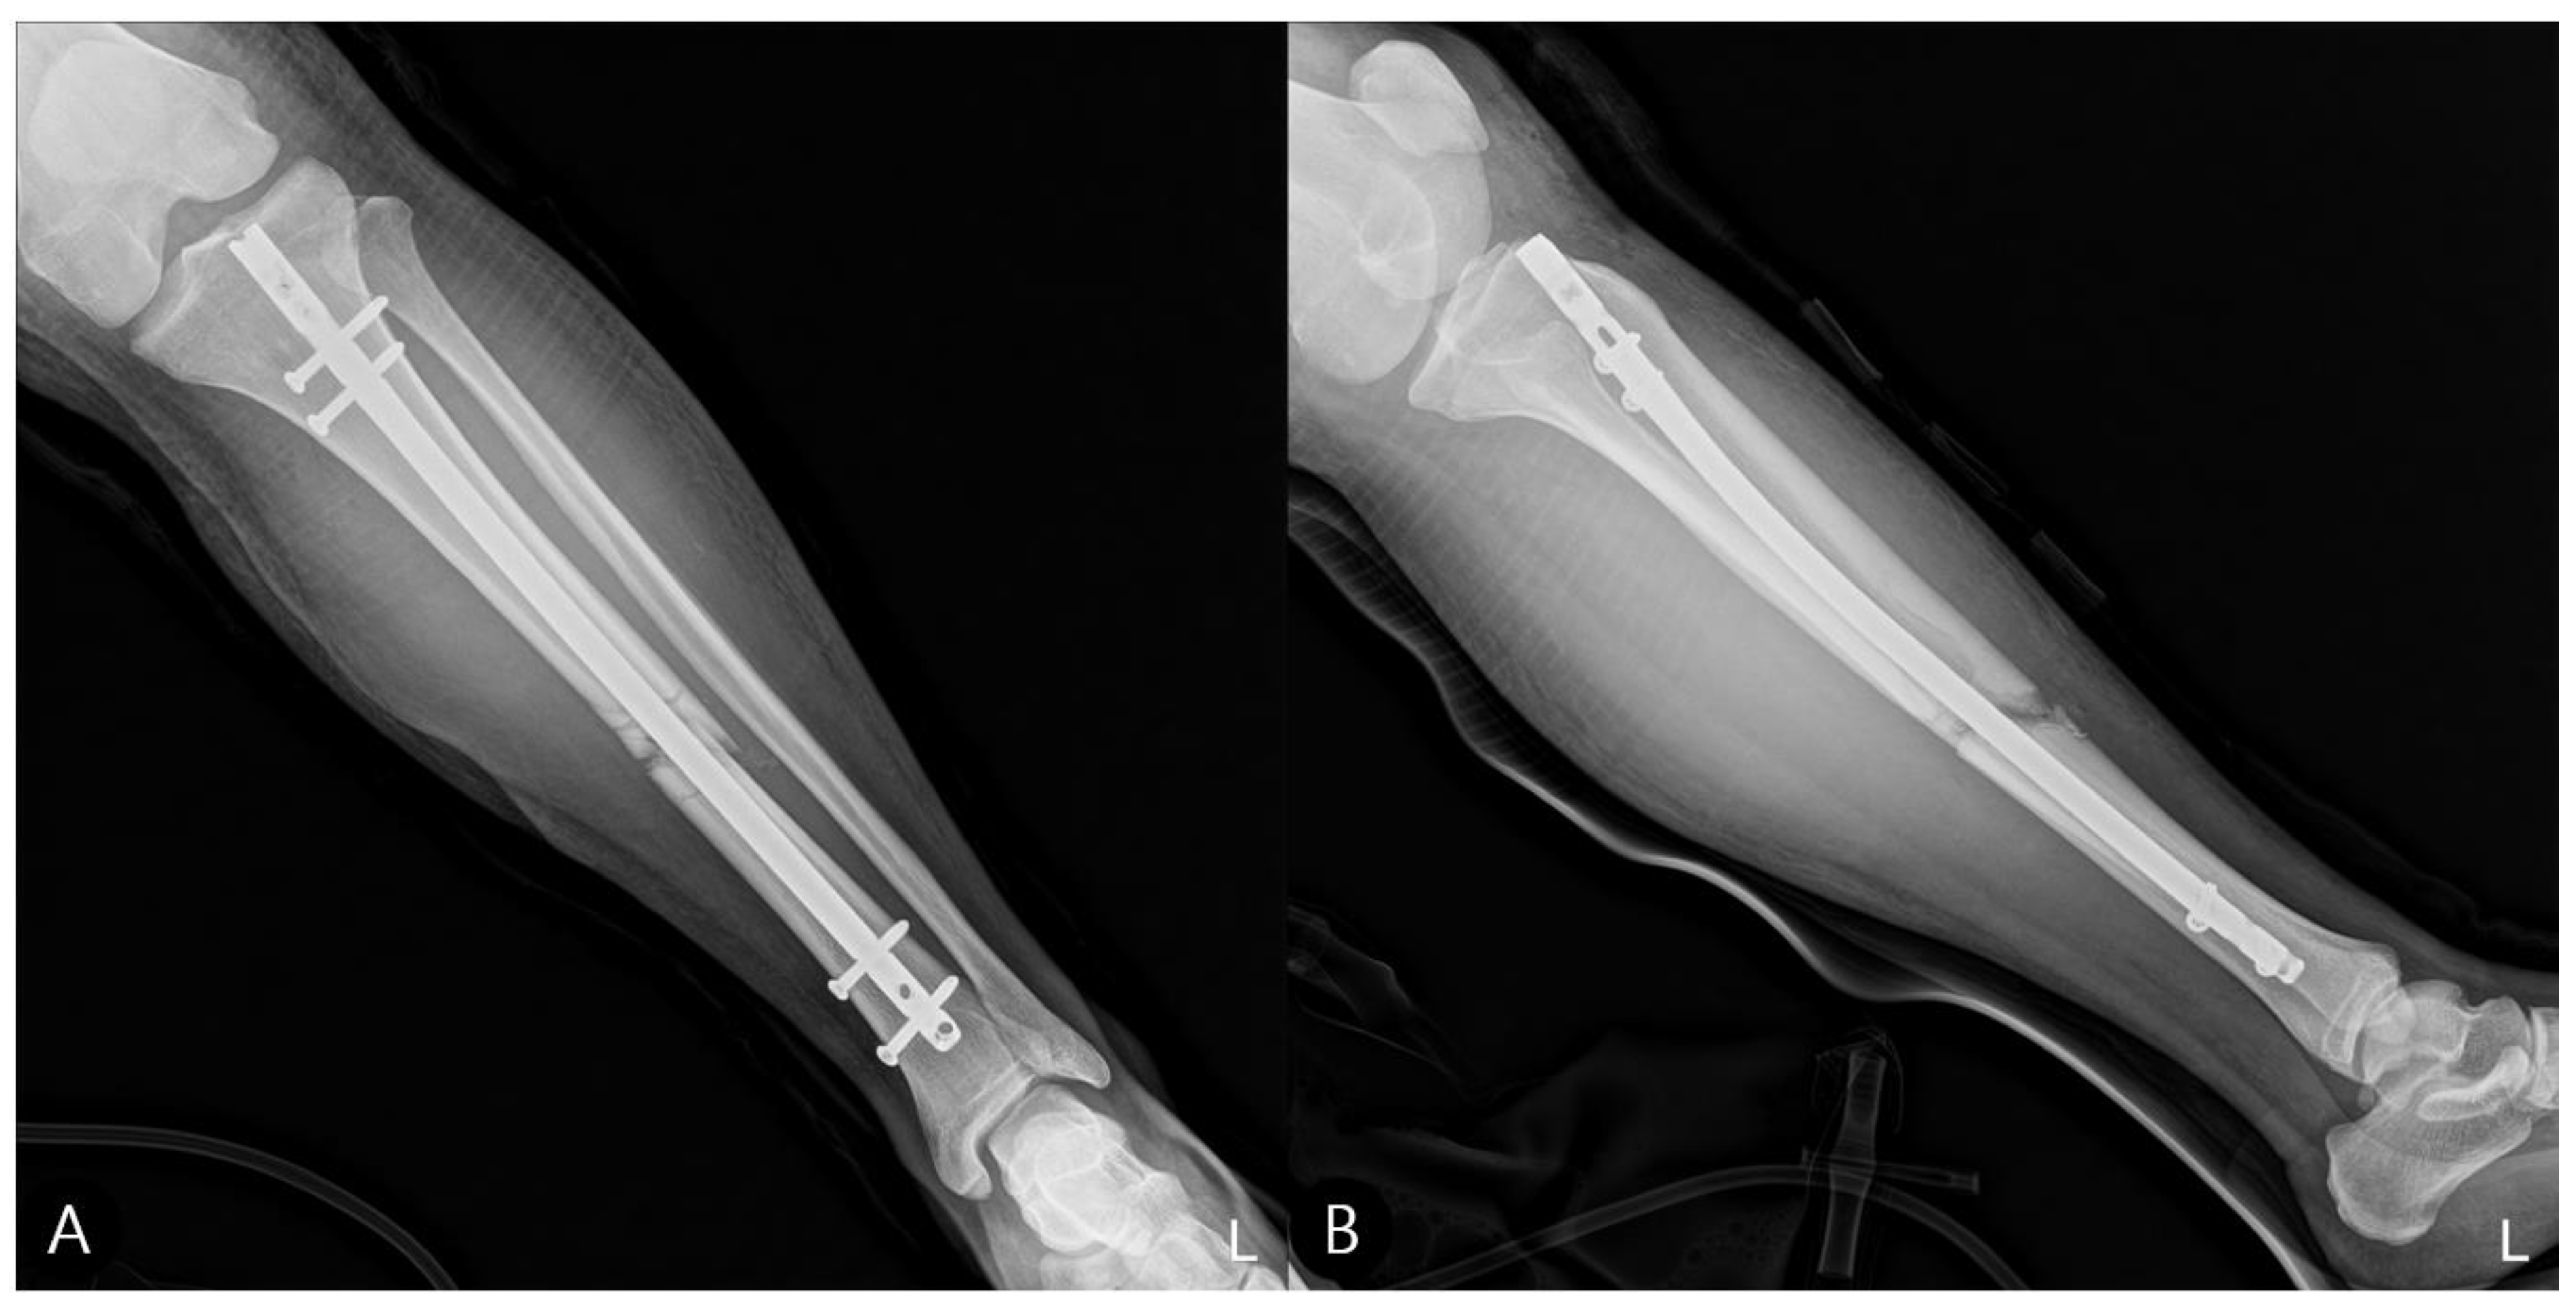

- Concomitant Injury Management:The tibial shaft fracture was subsequently stabilized with an antegrade intramedullary nail (Figure 6).